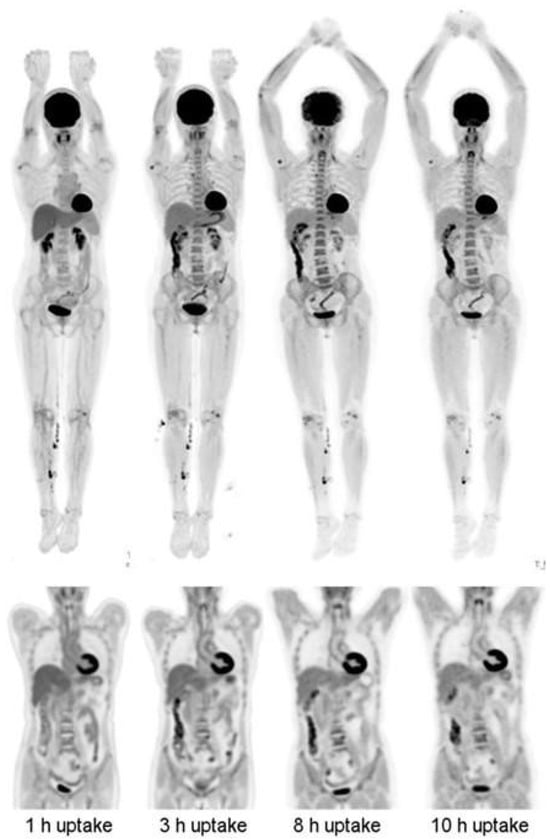

4. Longitudinal and Delayed Imaging

- Berg, E.; Gill, H.; Marik, J.; Ogasawara, A.; Williams, S.; van Dongen, G.; Vugts, D.; Cherry, S.R.; Tarantal, A.F. Total-Body PET and Highly Stable Chelators Together Enable Meaningful (89)Zr-Antibody PET Studies up to 30 Days After Injection. J. Nucl. Med. 2020, 61, 453–460. [Google Scholar] [CrossRef]

- Badawi, R.D.; Shi, H.; Hu, P.; Chen, S.; Xu, T.; Price, P.M.; Ding, Y.; Spencer, B.A.; Nardo, L.; Liu, W.; et al. First Human Imaging Studies with the EXPLORER Total-Body PET Scanner. J. Nucl. Med. 2019, 60, 299–303. [Google Scholar] [CrossRef]